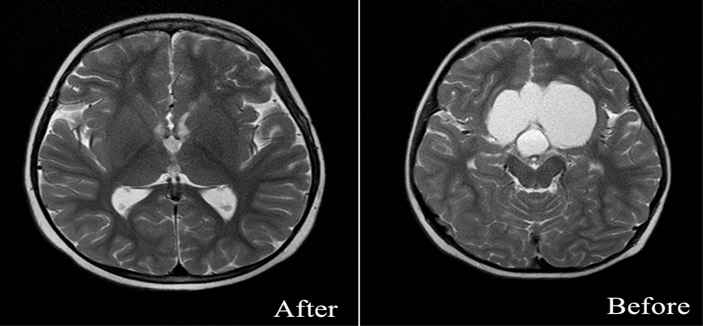

إنقاذ حياة طفل يعاني من ورم بالمخ لدى مستشفى د. سليمان الحبيب بالقصيم

تمكَّن فريق جراحي المخ والأعصاب بمستشفى د. سليمان الحبيب بالقصيم